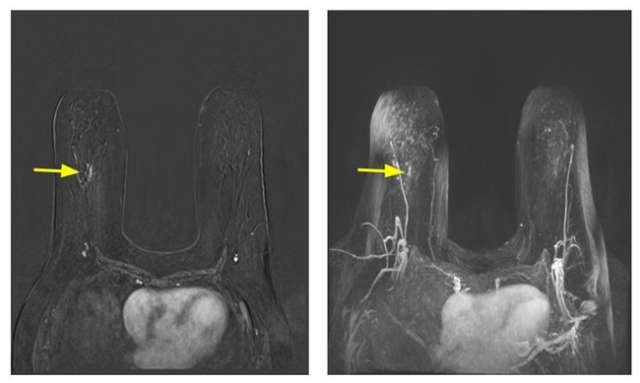

Mammography: High Risk Patient Population Figure 1

Figure 1. 59 year old female who presented for screening breast MRI due to her calculated lifetime risk of 20%. Post-contrast subtraction (left) and maximal intensity projection (right) images from MRI show nonmass enhancement in a linear distribution with a homogenous internal enhancement pattern in her right breast (yellow arrow), which is a BIRADS-4 finding. This area was subsequently biopsied and was turned out to be ductal carcinoma in situ. Of note, her prior mammogram from one year prior was negative. She was subsequently found to have CHEK2 germline mutation.